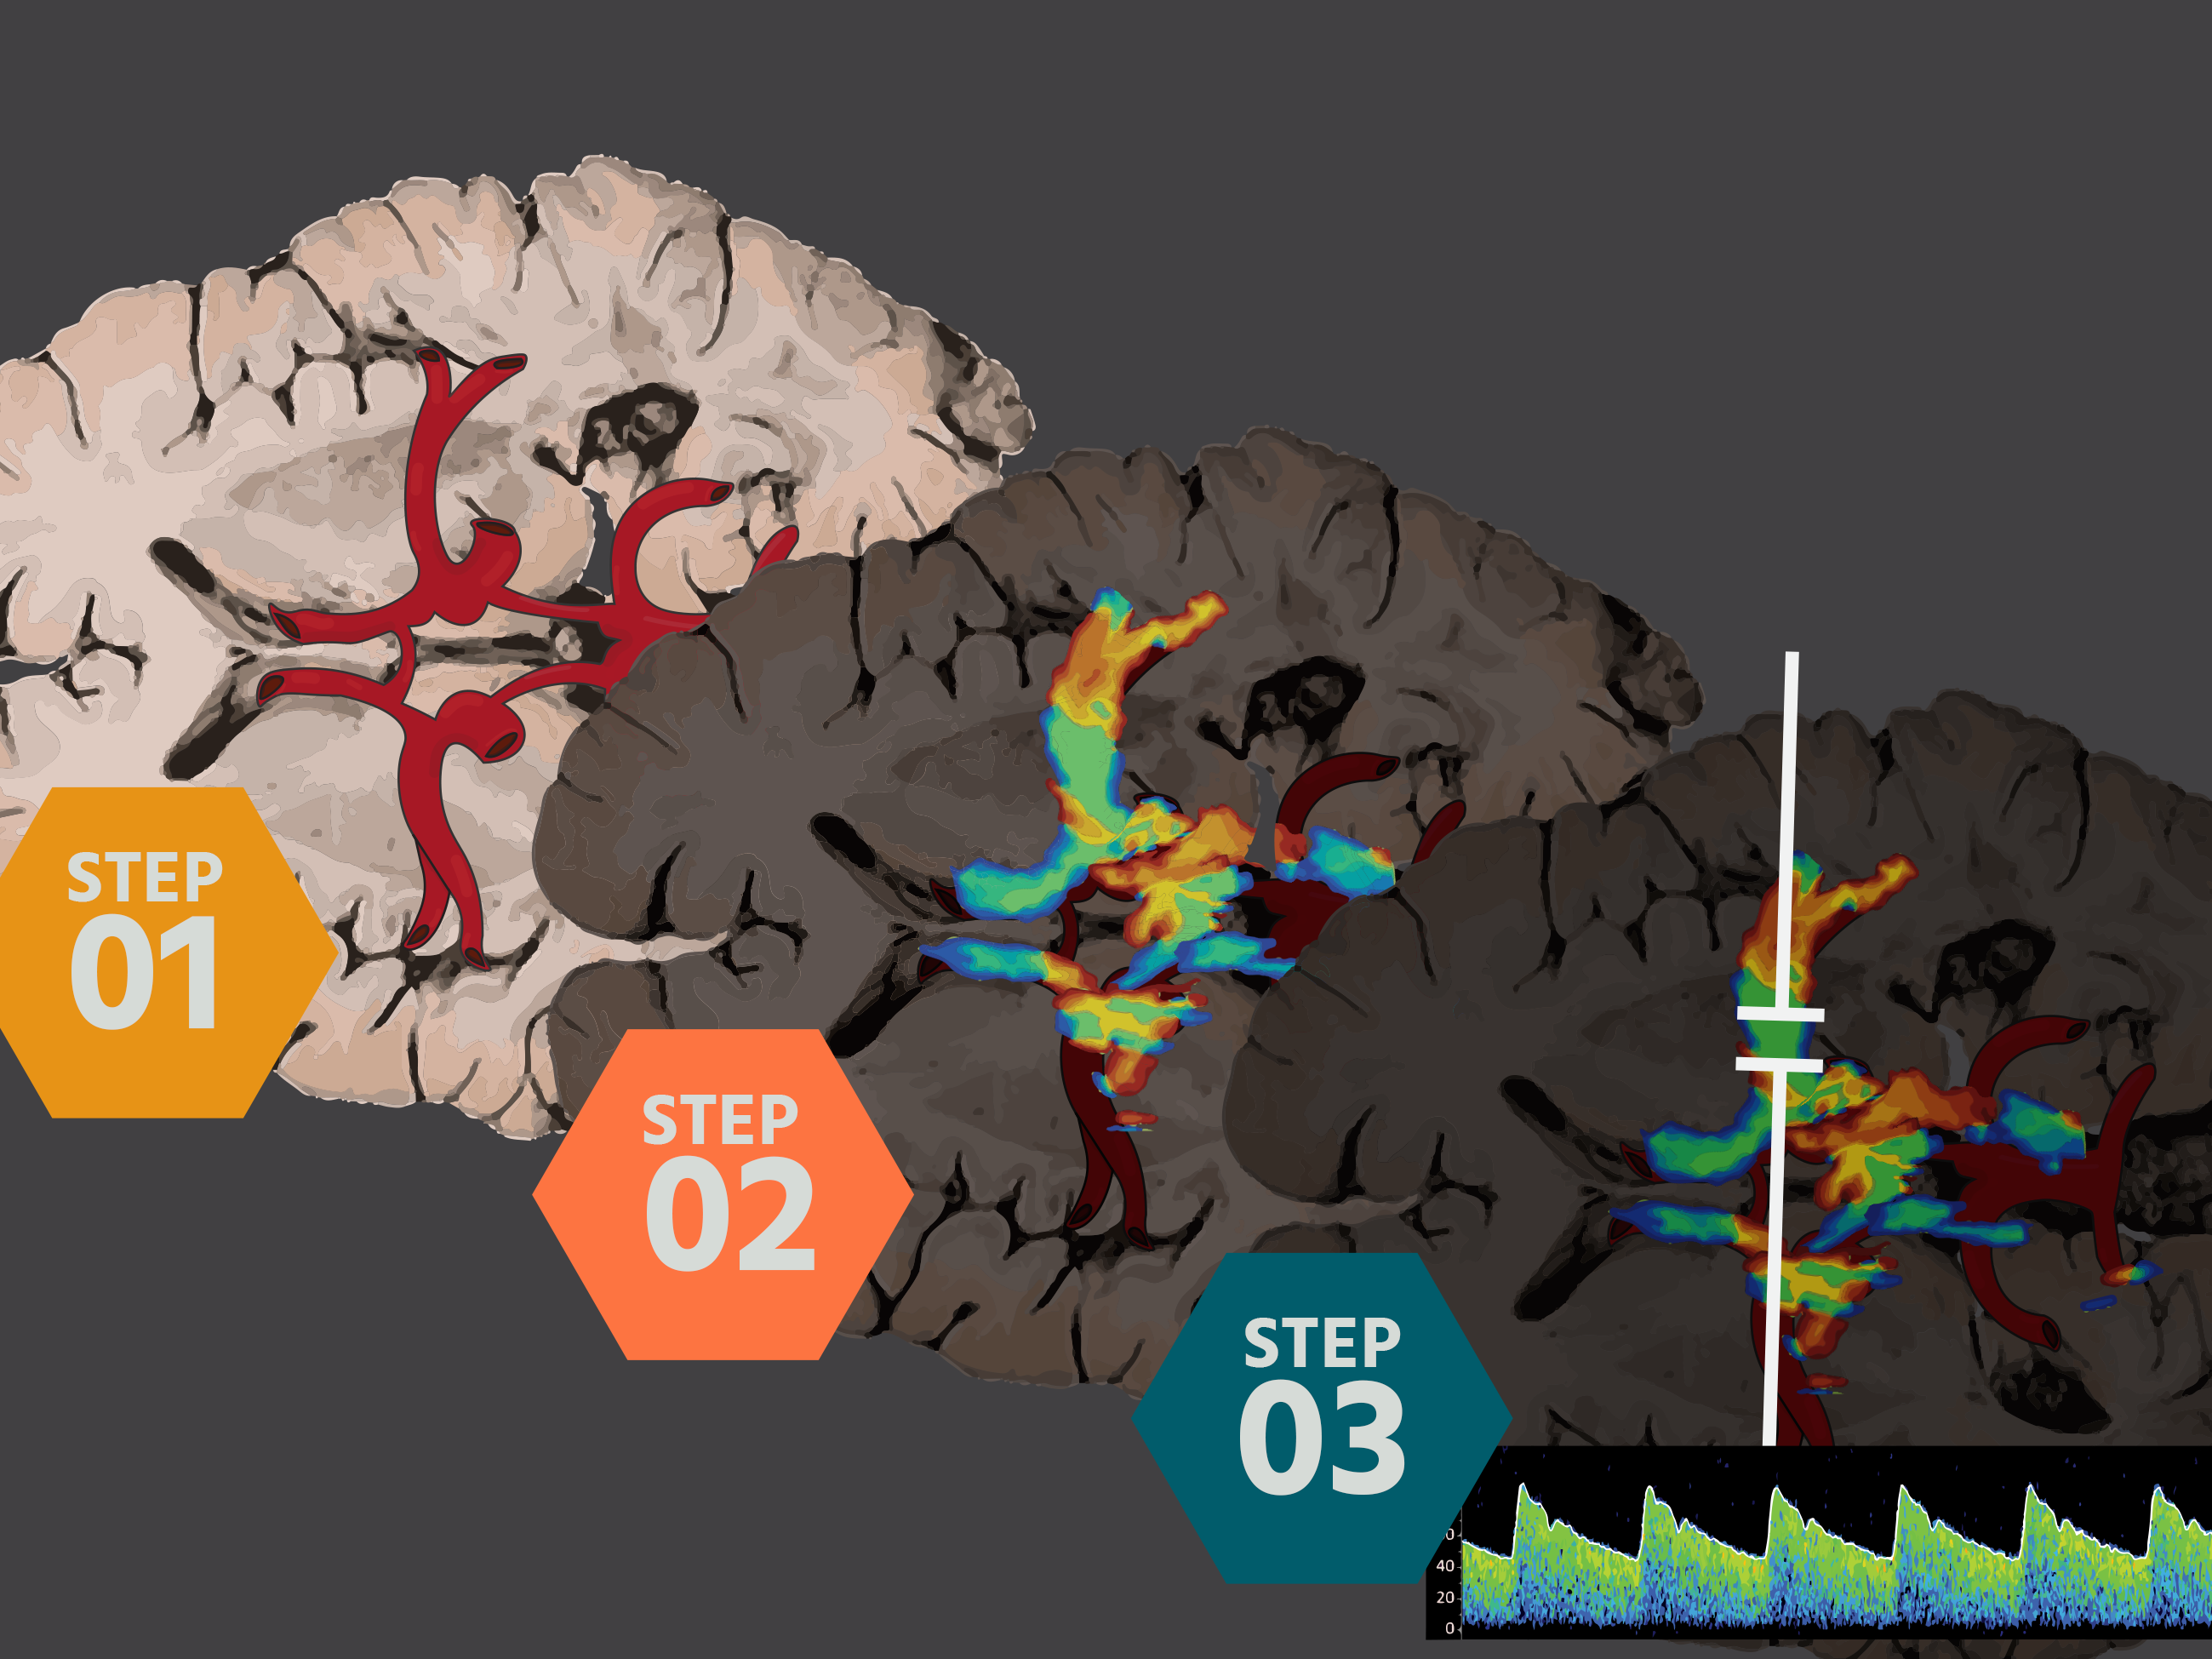

Midline Shift

Elevated Intracranial Pressure

Transcranial Ultrasound in Resuscitation